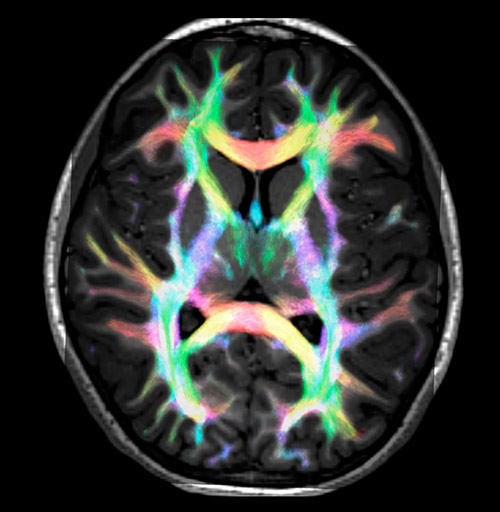

Super-resolution directionally encoded color track-density imaging overlaid on T1-weighted structural MRI.

All images were created from the same acquisition in a child using Ingenia 3.0T CX and 32-channel dS Head coil. Diffusion data was acquired at b-values 0, 500, 1000, 2000, 3000. The use of high b-values (3000 s/mm2) effectively suppresses extra-axonal water signal and provides high angular resolution.

Data processing was performed using open source software. Fiber tracking was performed using the MRtrix package (J-D Tournier, Brain Research Institute, Melbourne, Australia, https://github.com/MRtrix3/mrtrix3), Tournier et al. 2012. DEC TDI based on F Calamante et al 2010.